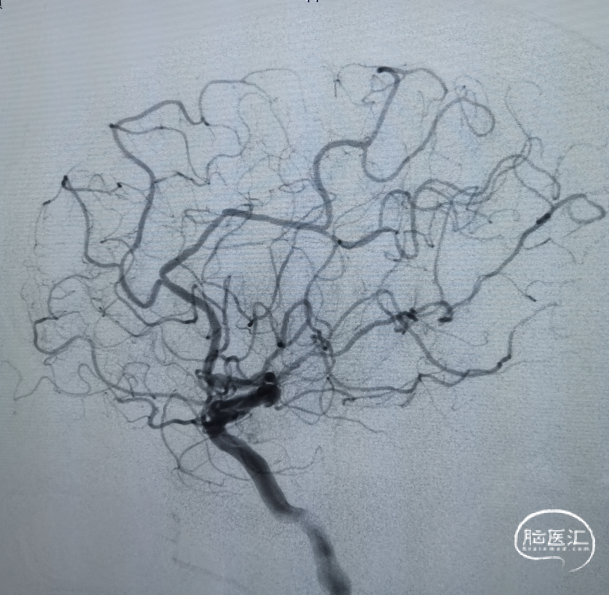

右侧颈动脉造影未见向左侧代偿。

左侧颈动脉造影提示左侧颈内动脉末端闭塞。

微导管置入左侧大脑中动脉M2段造影确认真腔。

置入一枚5*30mm 取栓支架造影。

充盈BGC球囊抽拉结合取栓一次。

支架联合抽吸可提高再通率;

使用BGC可减少远端栓塞事件,提高三级再通率;

BADDASS技术结合BGC、大口径中间导管和支架的优点,显著提高取栓一次再通率,实现快速三级再通。